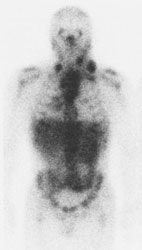

Gallium-67 imaging has been utilized for the evaluation of lymphoma, but the agent suffers from several limitations. First, the gallium exam requires several days to complete (PET exams are performed about 1 hour following injection of the agent). Second, the tumor-to-background ratio is higher for PET than for gallium [29]. Although probably adequate for imaging of the chest, gallium suffers from decreased sensitivity for evaluation of the abdomen due to high physiologic liver and bowl activity [1]. Third, due to its lower anatomic and spatial resolution, gallium imaging has decreased capability to detect small lesions when compared to FDG-PET imaging [1,4]. As a result of these limitations, up to 36% of lesions seen on PET images may not be visible on gallium exams [29]. Also, negative post-therapy gallium scans are not useful unless a pre-therapy scan demonstrating tumor accumulation of the agent were performed [7]. Post-therapy scans can also suffer from non-specific hilar uptake of gallium that can be confused for recurrent disease [8]. Overall, FDG PET exams are more sensitive than gallium imaging in the evaluation of lymphoma patients [22,26].

Gallium scan versus FDG PET exam: The exam on the left is from a gallium scan in a patient with lymphoma. Note the marked amount of background activity and lower spatial resolution compared to a FDG PET exam on an different lymphoma patient (back arrow points to nodal tracer uptake) |

|